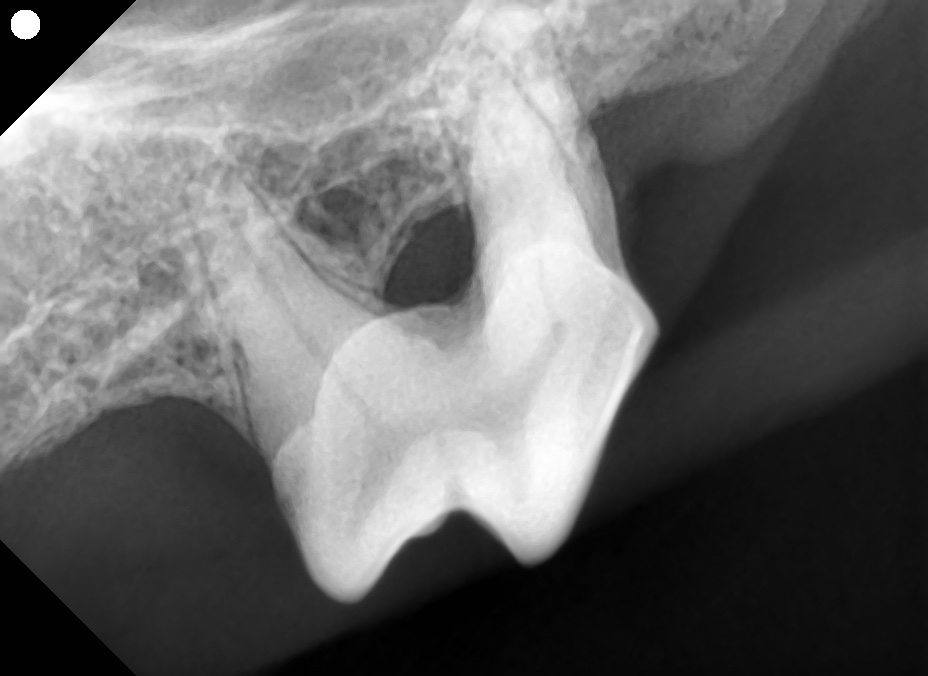

歯科レントゲンを撮影してみるとやはり歯槽骨の融解が進んでいました。

この歯はアタッチメントロスが50%以上、多根歯でステージⅢの根分岐病変を認めたため重度歯周病として抜歯が適応となります。